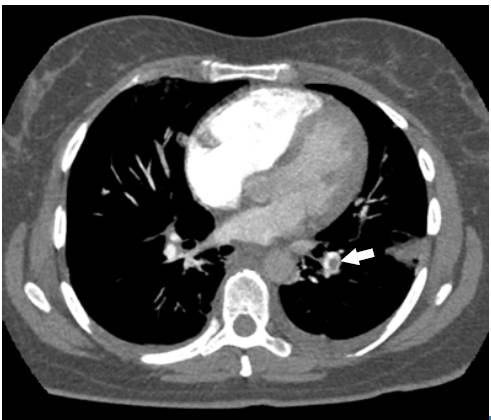

The Wells scale was applied, finding a high probability for pulmonary thromboembolism. Anticoagulation was initiated with low molecular weight heparin (enoxaparin) at a dose of 1 mg/kg every 12 hours, and a computed axial angiography (AngioCAT) of the chest was performed, confirming the diagnostic suspicion by reporting pulmonary artery obstruction in the trunk of the lower left basal segment (Figure 2).